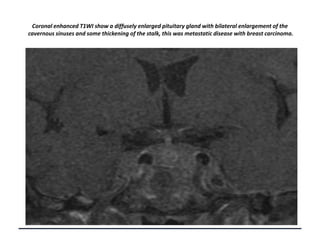

Coronal enhanced T1WI show a diffusely enlarged pituitary gland with bilateral enlargement of the

cavernous sinuses and some thickening of the stalk, this was metastatic disease with breast carcinoma.